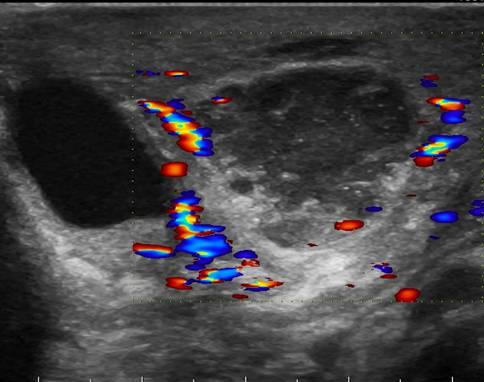

КТ диагностика тубоовариального абсцесса: Подходы и изображения

Раздел: Объективный взгляд